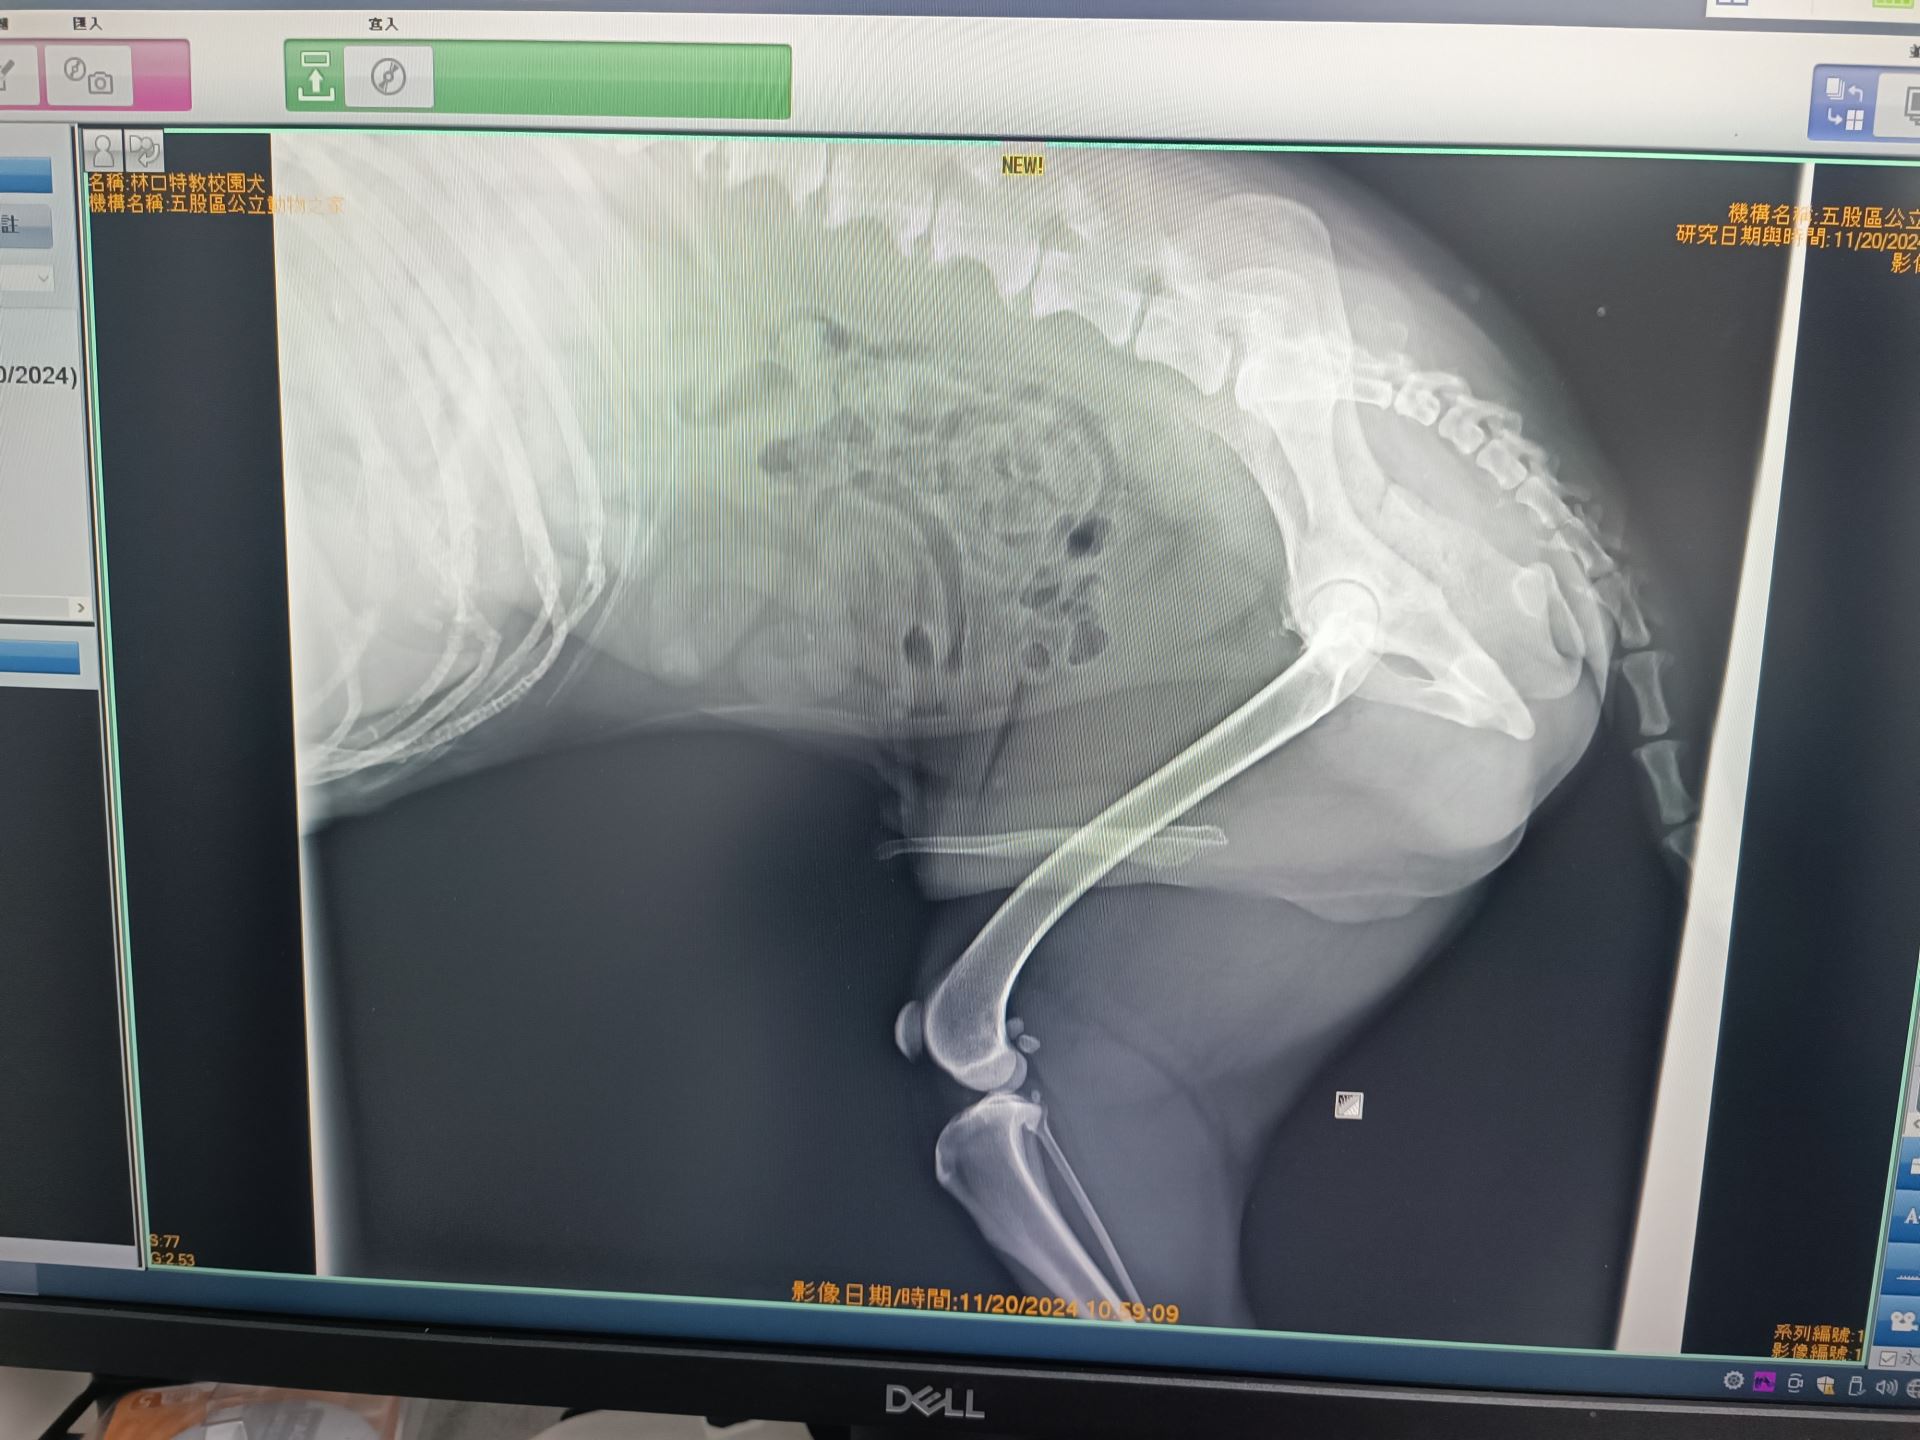

近期,新北市動保處為新北特殊教育學校的校園犬「貝果」進行例行健康檢查時,發現牠的肝功能指數偏高。

考量貝果已是14歲的高齡犬,經獸醫師詳細詢問主要照護人員梁老師並綜合評估後判定,肝指數升高可能屬於老化自然現象,目前暫無需用藥,只要定期追蹤即可。

後續回診顯示肝指數逐漸恢復正常,健康狀況穩定。

獸醫師林洋演進一步指出,老年犬肝功能異常的比例約為10%至20%,常見原因包括自然老化、感染、藥物副作用、環境毒素以及不當飲食等。